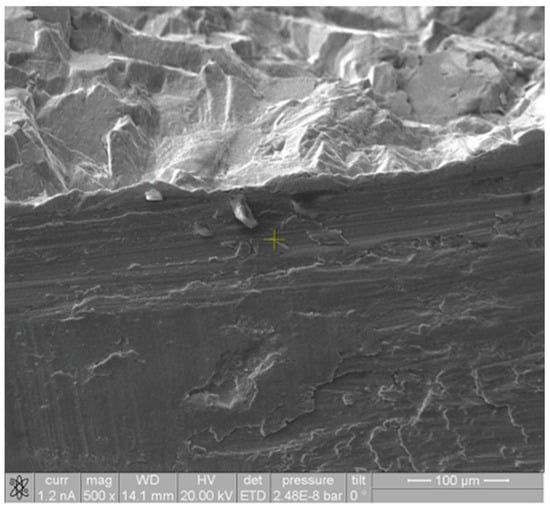

3.2.1. Fracture Surface

3.2.2. Lateral Surface